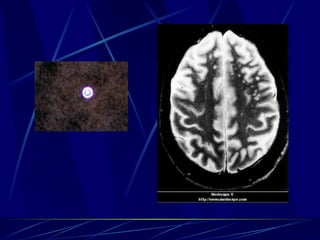

Cryptococcus neoformans Levadura encapsulada En tierra con heces de palomas Enfermedad Meningitis (Asociado a SIDA y Hodgkin’s) Neumonia aguda

Cryptococcus neoformans Diagnóstico: Antígeno Tinta china (50%) Cultivos (ureasa positivo) Tratamiento: AMB + 5FC hasta afebril y cultivo negativo y luego, fluconazol

Mucor Hongo filamentoso no septado en 90° Se encuentra en la tierra Enfermedad: Infección rinocerebral: edema paranasal, necrosis, exudados hemorrágicos, letargia En diabéticos y leucémicos Diagnóstico:  KOH  Tratamiento:  Debridar y AMB; alta RIP

Cryptococcus neoformans Levaduraencapsulada En tierra con heces de palomas Enfermedad Meningitis (Asociado a SIDA y Hodgkin’s) Neumonia aguda

Cryptococcus neoformans Diagnóstico:Antígeno Tinta china (50%) Cultivos (ureasa positivo) Tratamiento: AMB + 5FC hasta afebril y cultivo negativo y luego, fluconazol

Mucor Hongo filamentosono septado en 90° Se encuentra en la tierra Enfermedad: Infección rinocerebral: edema paranasal, necrosis, exudados hemorrágicos, letargia En diabéticos y leucémicos Diagnóstico: KOH Tratamiento: Debridar y AMB; alta RIP